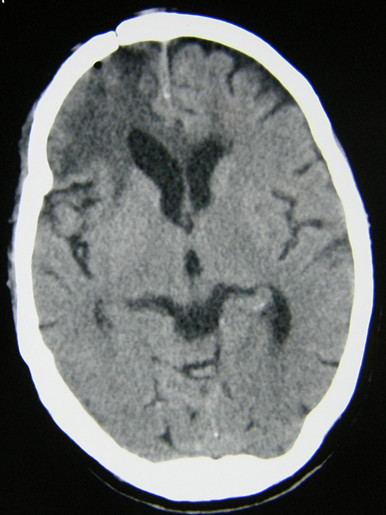

(2)增强扫描时,病灶局部可见增强肿块影,尤其是当非出血区强化则高度提示脑瘤卒中。因此,初次CT怀疑脑瘤卒中时,如果病情允许,建议复查CT及强化CT。MRI显示脑瘤卒中优于CT,若有条件最好做个MRI平扫加强化。见影像片3

影像片3:平扫及强化MRI比较。

患者女,77岁,因突发头痛、恶心、呕吐并意识不清2小时急诊入院。无高血压病史。查体:浅昏迷状,右侧瞳孔4mm,光反应弱。CT示:右额叶高低密度灶,中线移位。诊断:右额叶脑卒中并脑疝早期。行急症开颅术。

术后2天CT复查:病灶清除良好,中线恢复。患者神志恢复,四肢活动良好。

术后3周CT复查:水肿消退,肿瘤清除彻底。患者已下床活动并出院康复,嘱其定期复查酌情放疗。